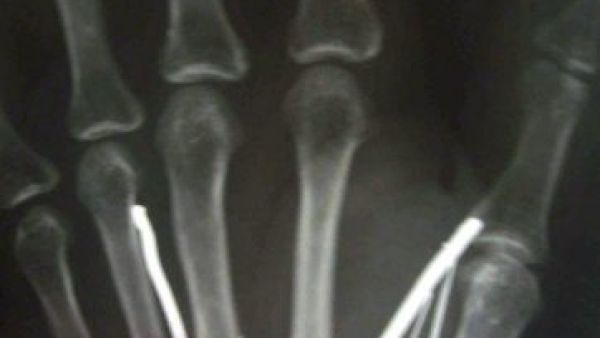

صورة اشعة ليد الخادمة السريلانكية تظهر وجود مسامير

ونجح الجراحون في مستشفى كامبوروبيتيا (جنوب سريلانكا) في انتزاع 19 مسمارا معدنيا من أصل 24 يصل طول بعضها إلى خمسة سنتيمترات بالإضافة إلى إبرة غرست في ذراعيها ورجليها وجبينها. أتى ذلك خلال عملية جراحية استمرت ثلاث ساعات.

ونقل غاجاديرا عنها أن "مخدومها أحمى المسامير المعدنية ومن ثم أدخلها في جسدها مستخدما المطرقة. أضاف أنهم وجدوا "المسامير في ذراعيها ورجليها وجبينها".

وكانت أرياواتي قد أدخلت إلى المستشفى في نهاية الأسبوع الماضي بعدما عادت إلى الديار وهي تشكو من آلام مبرحة، وقد عجزت عن السير. وتمكن الجراحون من انتزاع 13 مسمارا كبيرا كل واحد منها يبلغ خمسة سنتيمرات، بالإضافة إلى ستة مسامير صغيرة بحسب غاجاديرا. وأوضح أنه لم يتم نزع المسامير المتبقية لأنه كان من الممكن أن يتسبب ذلك بضرر في الأعصاب.